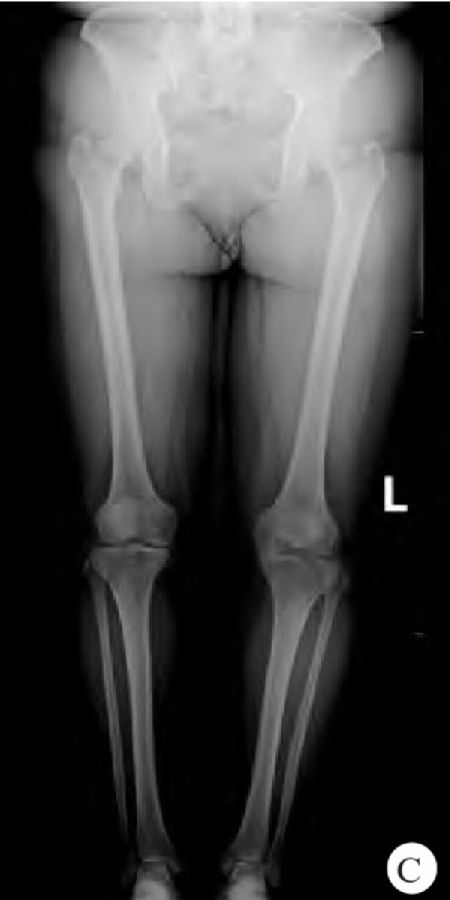

患者肥胖体形,身高145cm,体重72kg,体重指数34.2kg/m2,双膝部稍肿胀,局部皮肤完整,皮肤颜色、温度正常,双膝关节内侧膝关节间隙压痛明显,双膝关节活动度0°~140°,双下肢肌力及肌张力正常,双膝磨髌试验(−),过伸过屈试验(+),抽屉实验(−),侧方应力试验(−),麦氏试验(+),双下肢末梢血液循环及感觉未见明显异常,足背动脉均可触及。X线检查显示双膝内侧关节间隙减小(图1)。

图1 患者术前X线表现

A. 左膝关节正、侧位X线片显示左膝关节内侧间隙明显减小;B. 右膝关节正、侧位X线片显示右膝关节内侧间隙明显减小;C. 双下肢全长正位X线片显示双膝关节内侧间隙明显减小,左膝内侧间室已骨对骨摩擦。